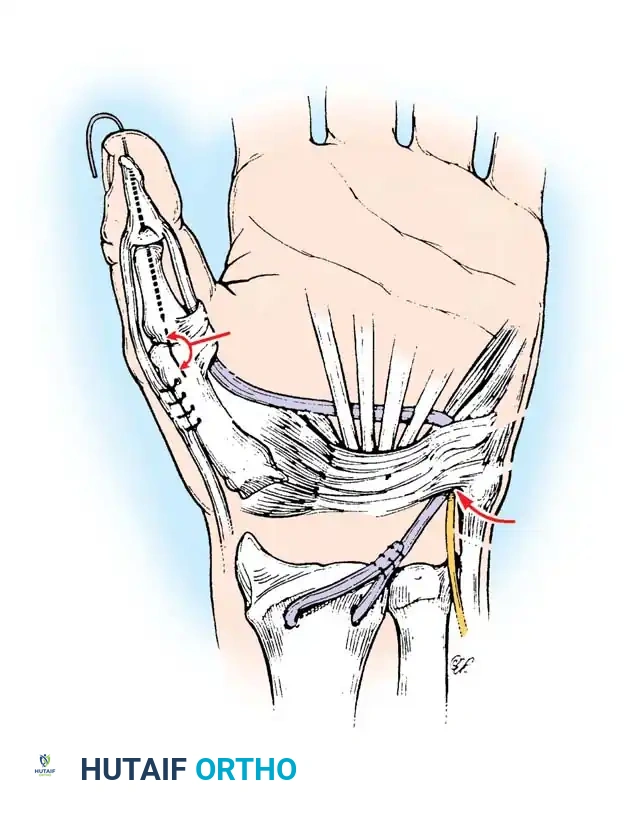

Moberg Key Grip Procedure

For Group 1 or Group 2 tetraplegics, the Moberg key grip procedure is foundational. This involves:

1. FPL Tenodesis: The FPL tendon is divided proximally and anchored to the distal radius. As the patient actively extends the wrist, the anchored FPL passively tightens, driving the thumb into lateral pinch against the index finger.

2. Thumb CMC Arthrodesis or Stabilization: To prevent the thumb from collapsing into retropulsion during pinch, the carpometacarpal (CMC) joint is often arthrodesed, or the metacarpophalangeal (MCP) joint is stabilized via capsulodesis or arthrodesis.

- Brachioradialis (BR) to FPL Transfer: The BR is an excellent donor for the FPL. It has immense power and adequate excursion. The BR must be mobilized extensively, proximal to the elbow joint, to maximize its amplitude.

Intrinsic Balancing and the Zancolli Lasso

Tetraplegic hands are inherently "intrinsic-minus," leading to clawing of the fingers (hyperextension of the MCP joints and flexion of the IP joints). This posture defeats the tenodesis effect, as the fingers roll up into the palm rather than sweeping in a wide arc to grasp objects.

To correct this, the Zancolli lasso procedure or similar intrinsic stabilizations are performed. The Flexor Digitorum Superficialis (FDS) tendons are divided distally, looped around the A1 or A2 pulleys, and sutured back onto themselves. This creates a static volar tenodesis that prevents MCP hyperextension, ensuring that proximal pull on the FDP translates into a functional sweeping grasp.